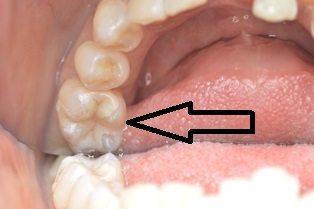

2016年4月26日 / 最終更新日時 : 2019年7月1日 まえだ歯科 ブログ ジルコニアインレー 術前 術後 下の奥歯にジルコニアインレーをセットしました。ジルコニアも材質が改良されてきて、いい色が出るようになってきました。 歯科医師 前田